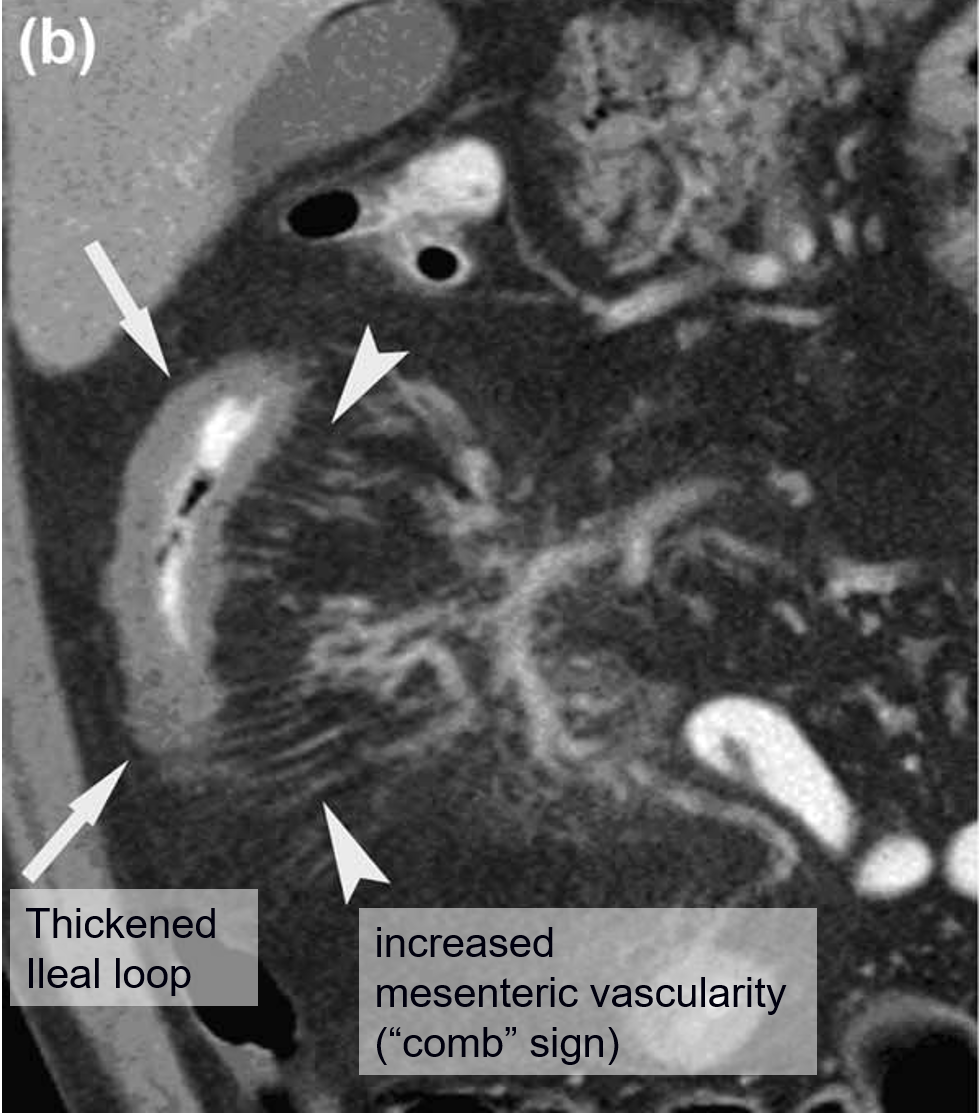

صورة CTE مميزة:

صورة MRE مميزة: